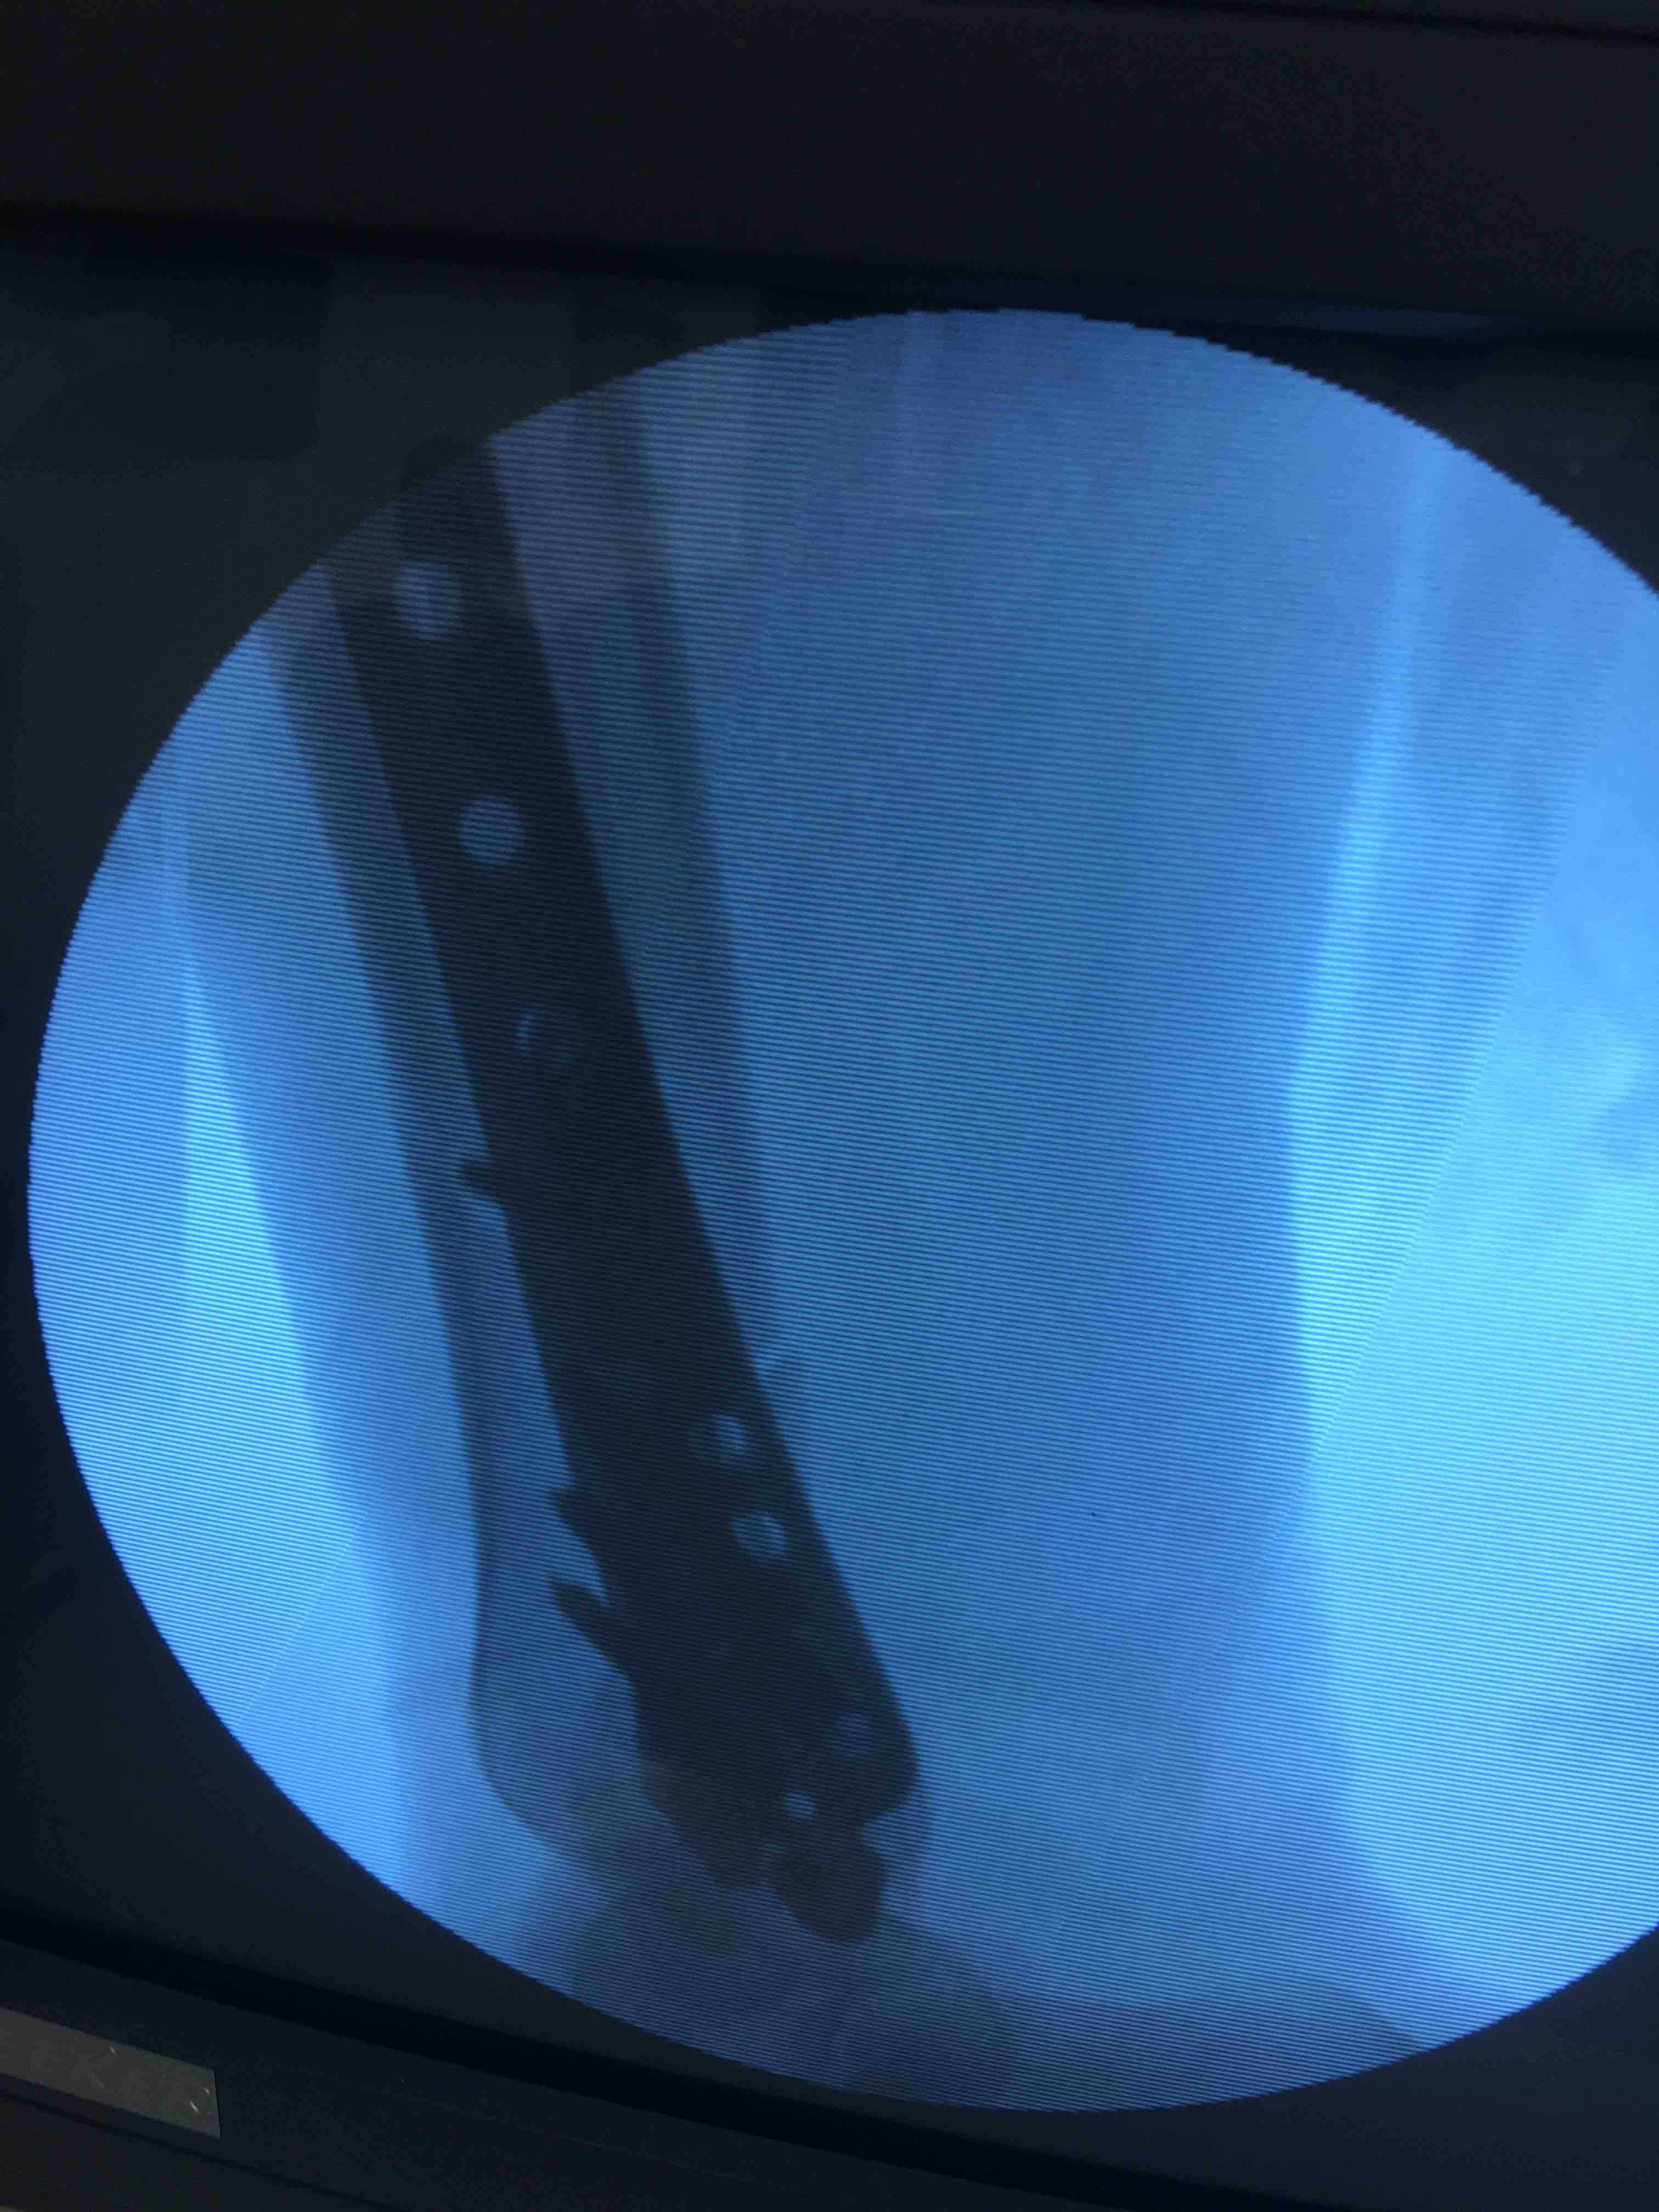

胫腓骨下段骨折(微创固定)

摔伤后右小腿肿痛,活动受限1小时入院。既往身体健康,无特殊不良嗜好。

生命体征平稳,心肺复未见明显异常。右小腿肿胀,局部皮色皮温正常,压痛及叩痛阳性,可及骨擦音,活动受限,末梢血运感觉正常。

在腰麻下行切复内固定术,术后抗炎,消肿对症治疗。